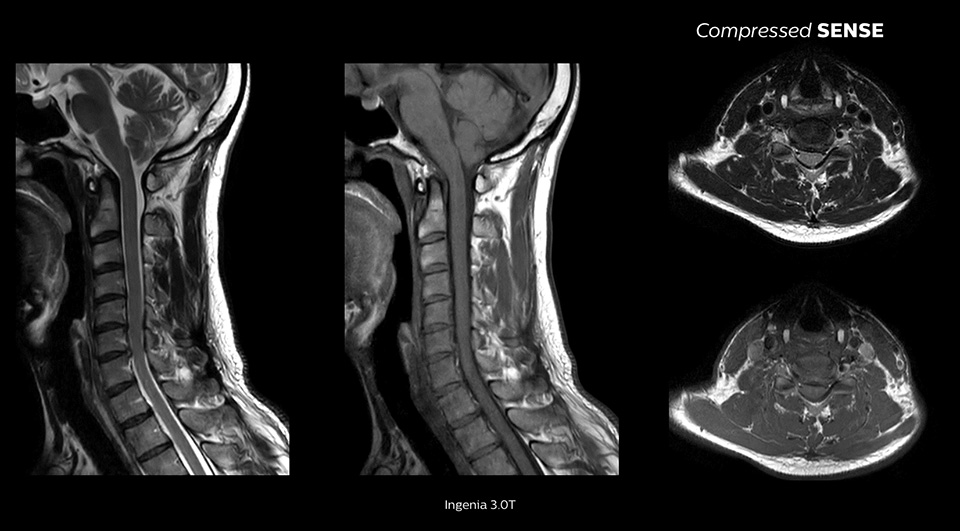

We are essentially running our standard protocols and just turning Compressed SENSE on and seeing a 20% reduction in scan time. None of the physicians know if it’s a Compressed SENSE scan versus a non-Compressed SENSE scan when they’re reading."

John P. Karis, M.D. Director of MRI and brain imaging, Department of Neuroradiology at Barrow Neurological Institute, USA

Enables up to 64% improvement in spatial resolution1